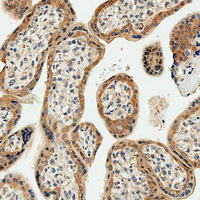

Immunohistochemical analysis of DKK1 staining in human placenta tissue formalin fixed paraffin embedded tissue section. The section was pre-treated using heat mediated antigen retrieval with sodium citrate buffer (pH 6.0). The section was then incubated with the antibody at room temperature and detected using an HRP conjugated compact polymer system. DAB was used as the chromogen. The section was then counterstained with haematoxylin and mounted with DPX. -